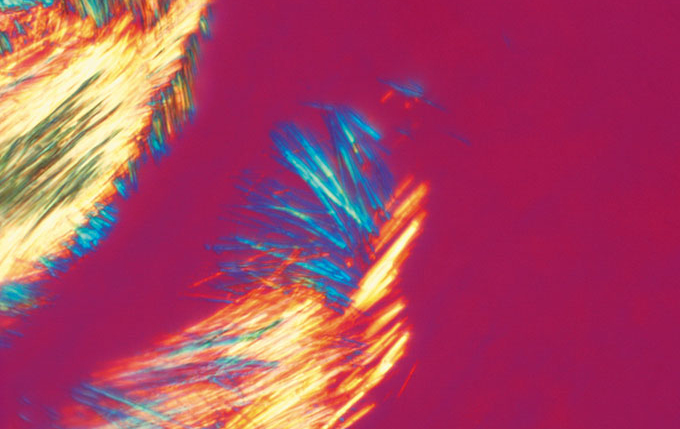

简易偏光

使用简易的偏光聚光镜、一个检偏镜和偏光物镜可以在4×至100×下进行偏光观察。

简易偏光:尿酸晶体

简易偏光聚光镜/ CH3-CDP

奥林巴斯显微镜CX41通过可选配的平板适配器U-TAD,可以使用补色器在4×至100×倍率条件下进行偏光观察。 提供了专用于痛风诊断的U-GAN检偏镜。 可以使用4×至100×的偏光物镜。